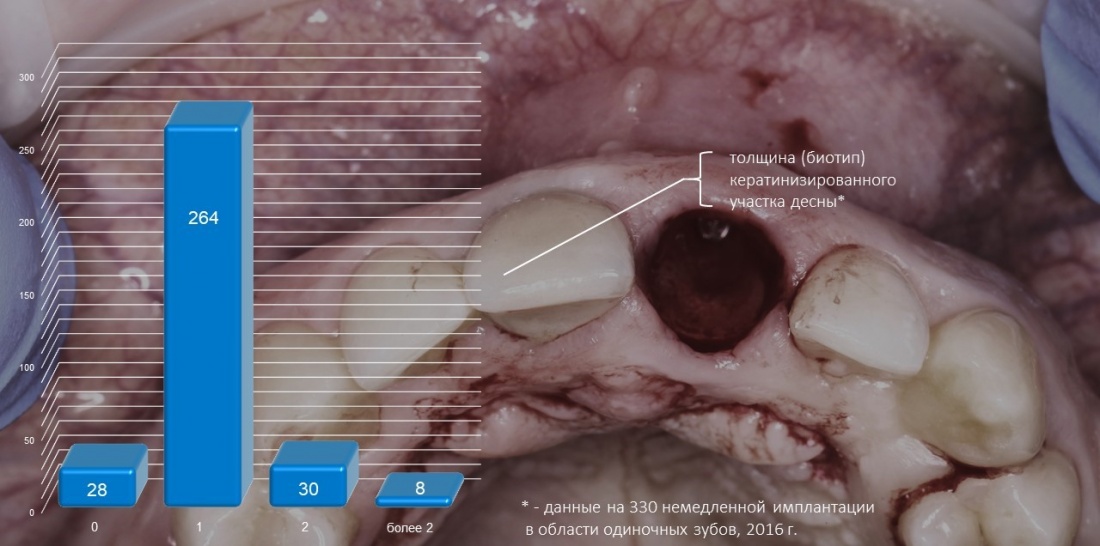

На каждую проводимую операцию мы оформляли чек-лист, в котором отмечали практические параметры десны, ширину кератинизированного участка L и биотип D. У нас получились следующие результаты:

по ширине кератинизированного участка L:

и по биотипу D: